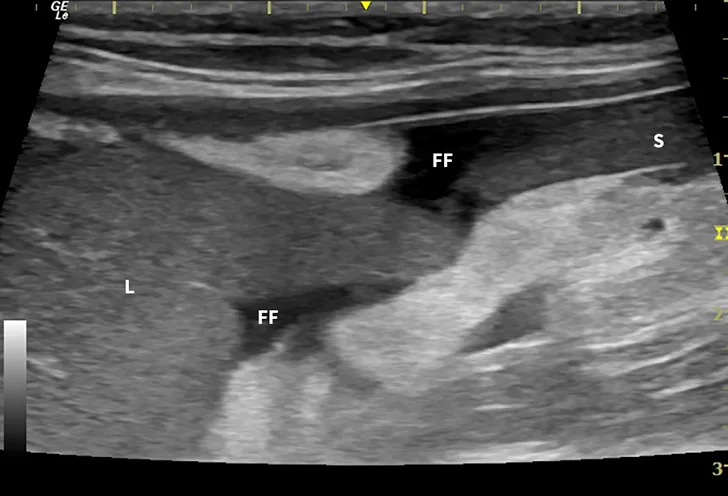

Dry FIP can manifest with organ dysfunction, uveitis, neurologic signs, fever, anemia, and/or lethargy and is caused by granulomas or immune complex deposition. Cats with wet FIP may have ascites or pleural effusion in addition to the aforementioned signs (Figure 1). Clinical presentation can vary from minor to life-threatening and involve almost any organ system.

FIGURE 1

Ultrasound image showing abdominal effusion in a cat with wet FIP. Anechoic fluid is present between organs, distending the abdomen. FF = free fluid; L = liver; S = spleen; K = kidney